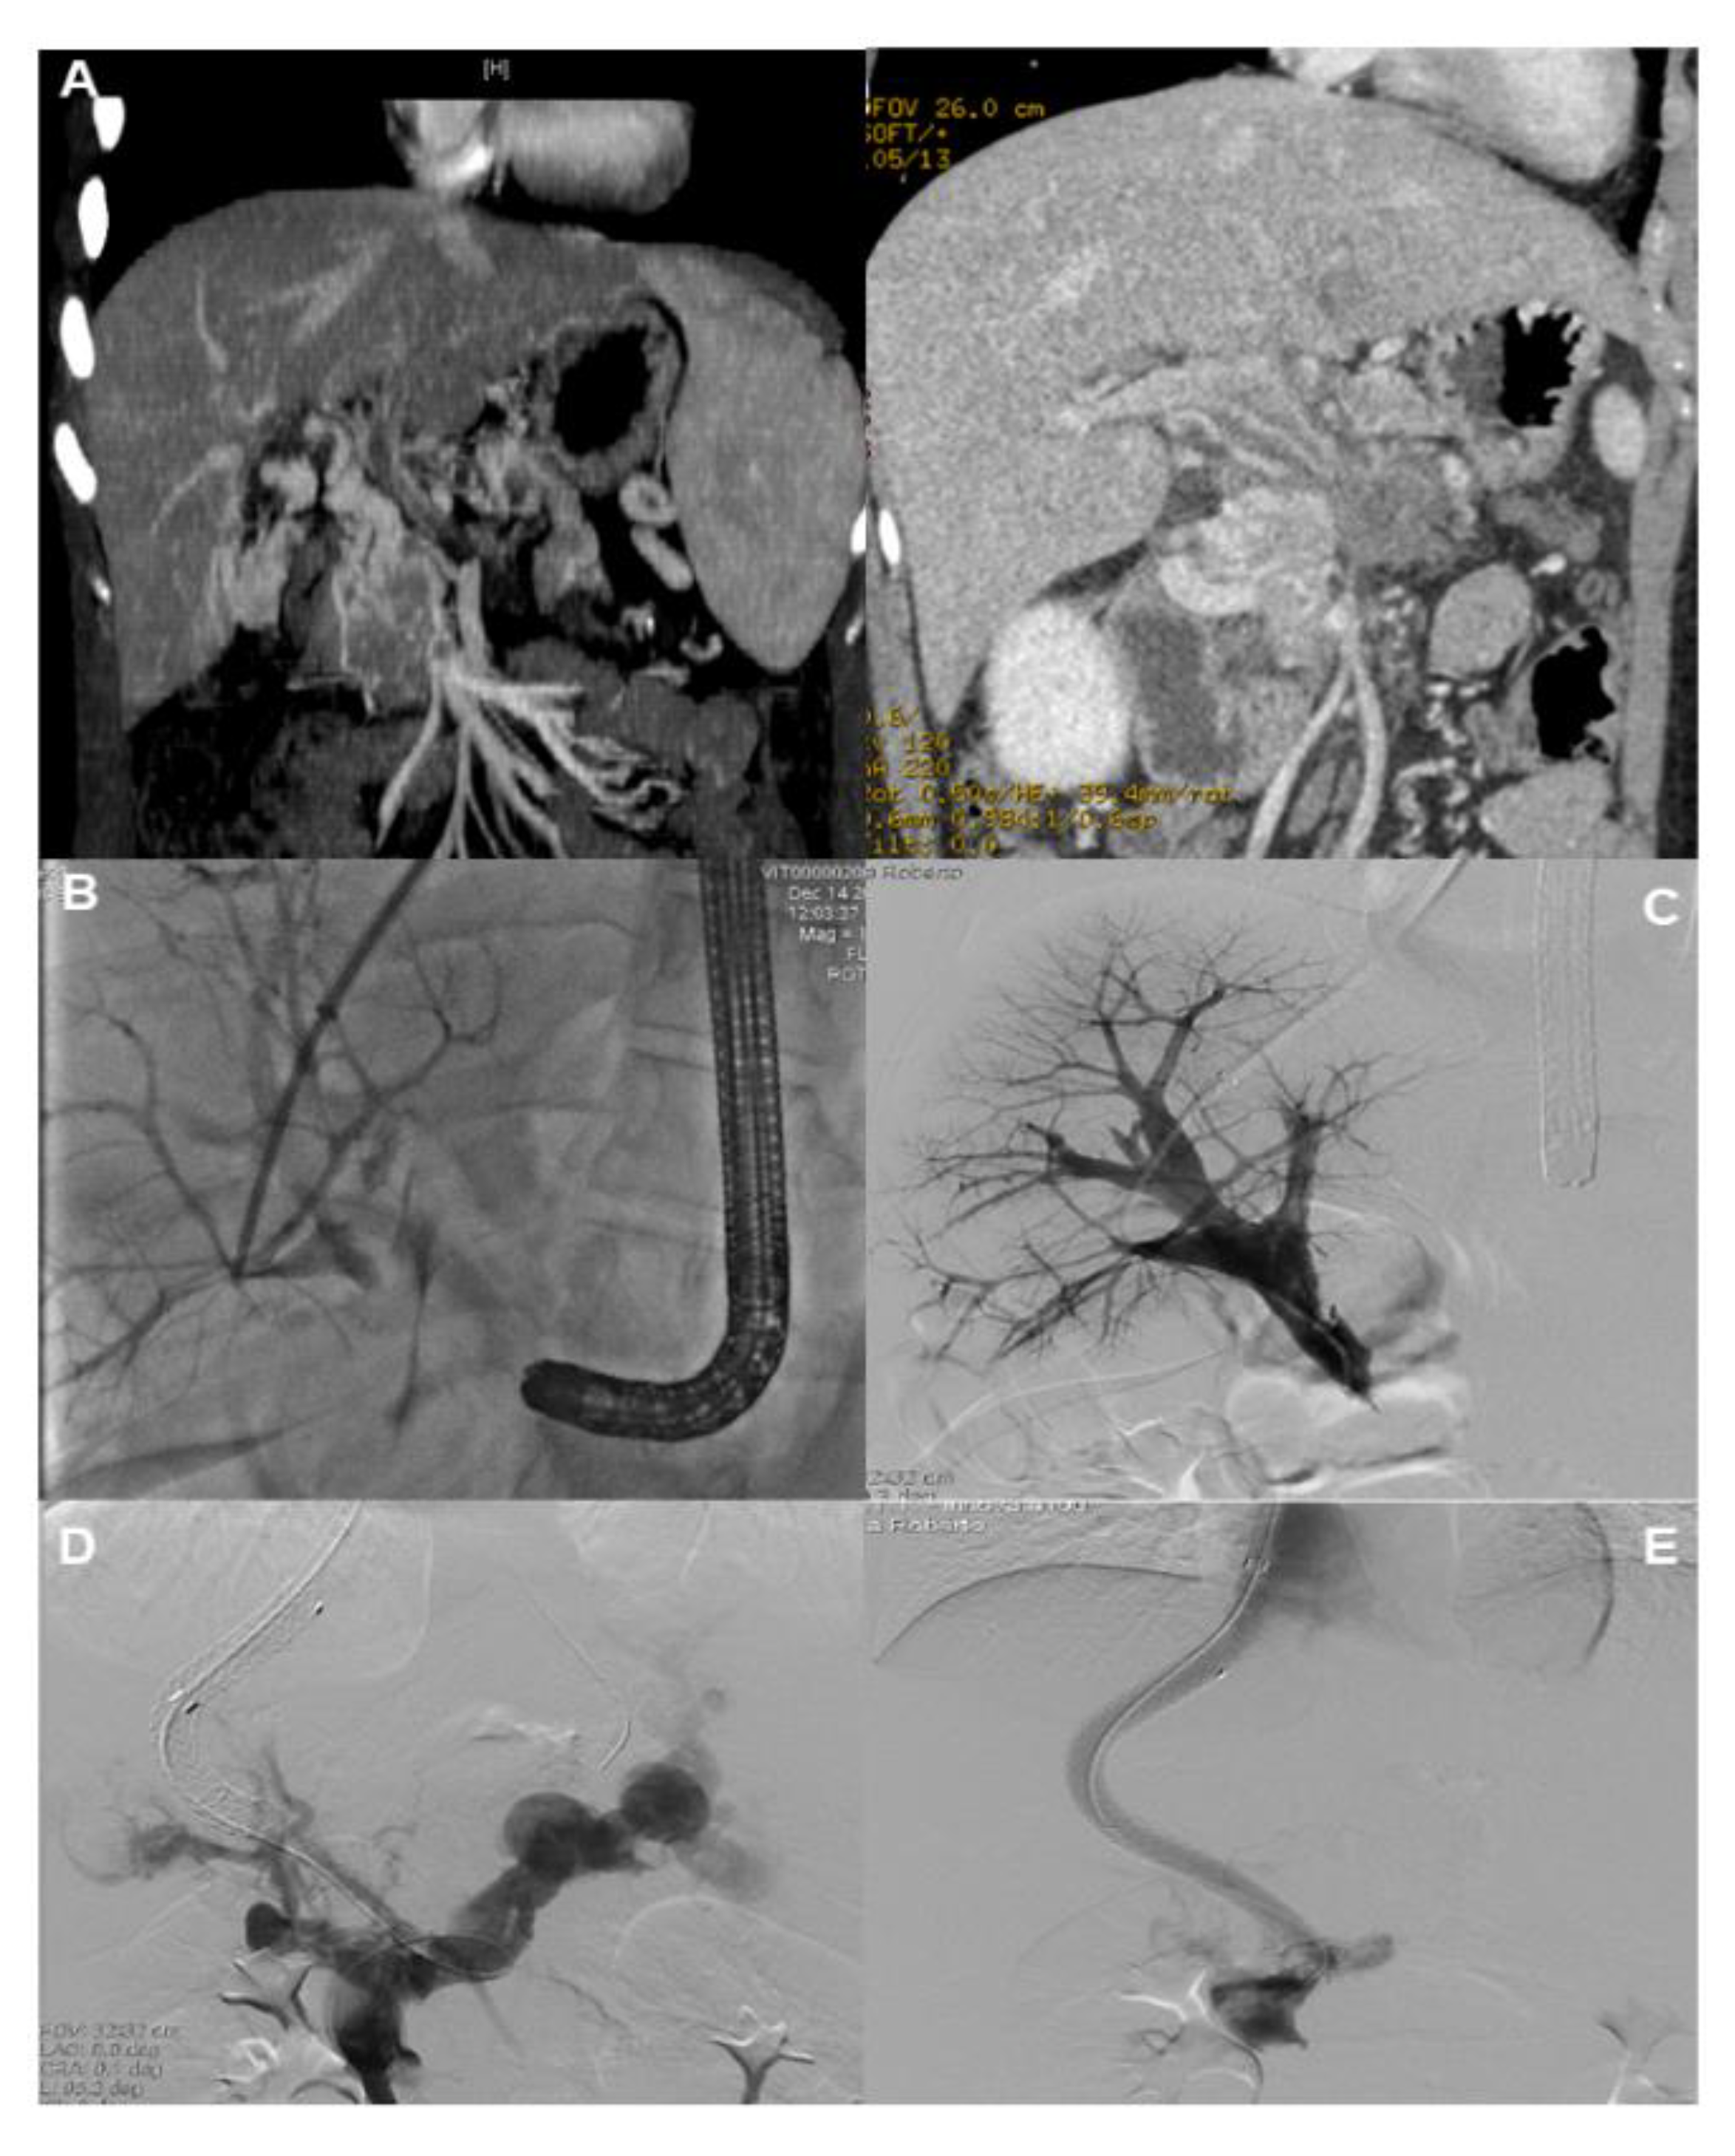

- Miraglia, R.; Maruzzelli, L.; Cannataci, C.; Gerasia, R.; Mamone, G.; Cortis, K.; Cimo, B.; Petridis, I.; Volpes, R.; Luca, A. Radiation exposure during transjugular intrahepatic portosystemic shunt creation in patients with complete portal vein thrombosis or portal cavernoma. Radiol. Med. 2020, 125, 609–617. [Google Scholar] [CrossRef]

- Chen, Y.; Ye, P.; Li, Y.; Ma, S.; Zhao, J.; Zeng, Q. Percutaneous transhepatic balloon-assisted transjugular intrahepatic portosystemic shunt for chronic, totally occluded, portal vein thrombosis with symptomatic portal hypertension: Procedure technique, safety, and clinical applications. Eur. Radiol. 2015, 25, 3431–3437. [Google Scholar] [CrossRef]

- Entezari, P.; Riaz, A.; Thornburg, B.; Salem, R. Percutaneous Ultrasound-Guided Superior and Inferior Mesenteric Vein Access for Portal Vein Recanalization-Transjugular Intrahepatic Portosystemic Shunt: A Case Series. Cardiovasc. Intervent. Radiol. 2021, 44, 496–499. [Google Scholar] [CrossRef]

- Steffen, D.A.; Najafi, A.; Binkert, C.A. Safety of Percutaneous Transmesenteric and Transsplenic Access for Portosystemic Shunt Creation in Patients with Portal Vein Obstruction: Single-Center Experience and Review of Literature. Cardiovasc. Intervent. Radiol. 2023, 46, 1401–1406. [Google Scholar] [CrossRef]

- Thornburg, B.; Desai, K.; Hickey, R.; Hohlastos, E.; Kulik, L.; Ganger, D.; Baker, T.; Abecassis, M.; Caicedo, J.C.; Ladner, D.; et al. Pretransplantation Portal Vein Recanalization and Transjugular Intrahepatic Portosystemic Shunt Creation for Chronic Portal Vein Thrombosis: Final Analysis of a 61-Patient Cohort. J. Vasc. Interv. Radiol. 2017, 28, 1714–1721. [Google Scholar] [CrossRef]

- Bilbao, J.I.; Elorz, M.; Vivas, I.; Martinez-Cuesta, A.; Bastarrika, G.; Benito, A. Transjugular intrahepatic portosystemic shunt (TIPS) in the treatment of venous symptomatic chronic portal thrombosis in non-cirrhotic patients. Cardiovasc. Intervent. Radiol. 2004, 27, 474–480. [Google Scholar] [CrossRef]

- Fanelli, F.; Angeloni, S.; Salvatori, F.M.; Marzano, C.; Boatta, E.; Merli, M.; Rossi, P.; Attili, A.F.; Ridola, L.; Cerini, F.; et al. Transjugular intrahepatic portosystemic shunt with expanded-polytetrafuoroethylene-covered stents in non-cirrhotic patients with portal cavernoma. Dig. Liver Dis. 2011, 43, 78–84. [Google Scholar] [CrossRef]

- Klinger, C.; Riecken, B.; Schmidt, A.; De Gottardi, A.; Meier, B.; Bosch, J.; Caca, K. Transjugular portal vein recanalization with creation of intrahepatic portosystemic shunt (PVR-TIPS) in patients with chronic non-cirrhotic, non-malignant portal vein thrombosis. Z. Gastroenterol. 2018, 56, 221–237. [Google Scholar] [CrossRef]